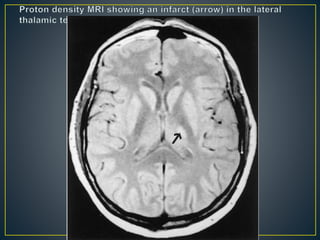

• Infarcts in the lateral territory of the thalamus are associated

with occlusion of the anterior choroidal branch of the internal

carotid artery.

• Structures involved in the lesion include the posterior limb of

the internal capsule, lateral thalamic nuclei (lateral geniculate,

ventral posterior lateral, pulvinar, reticular), and medial

temporal lobe.

• The clinical hallmarks of the infarct are contralateral

hemiparesis and dysarthria.

• Lesions in the lateral thalamic territory may manifest with only

pure motor hemiparesis.

• Other clinical manifestations include hemisensory loss of pain

and touch, occasional visual field defects, and

neuropsychological defects.

• The latter consist of memory defects in left-sided lesions and

visuospatial defects in right-sided lesions